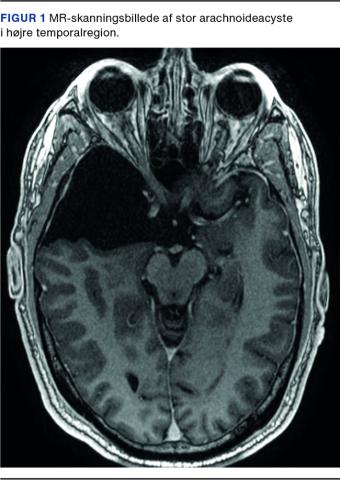

Arachnoideacyster (Figur 1 og Figur 2) er hyppige tilfældige fund på hjerneskanninger med en prævalens på 2% i befolkningen [1]. De betragtes som kongenitte strukturer, som udgår fra arachnoidea mater, den midterste hjernehinde, og indeholder cerebrospinalvæske. De kan opstå overalt, hvor der findes arachnoidea, inklusive i spinalkanalen. De intrakranielle arachnoideacyster ses oftest i fossa cranii media (55%), hvor de typisk er placeret mellem cerebrum og kraniet [1]. De findes her lidt hyppigere i venstre end i højre hemisfære, og blandt patienterne ses en lille overvægt af mænd [2].

MR-skanningsbillede af stor arachnoideacyste i venstre temporal­region.